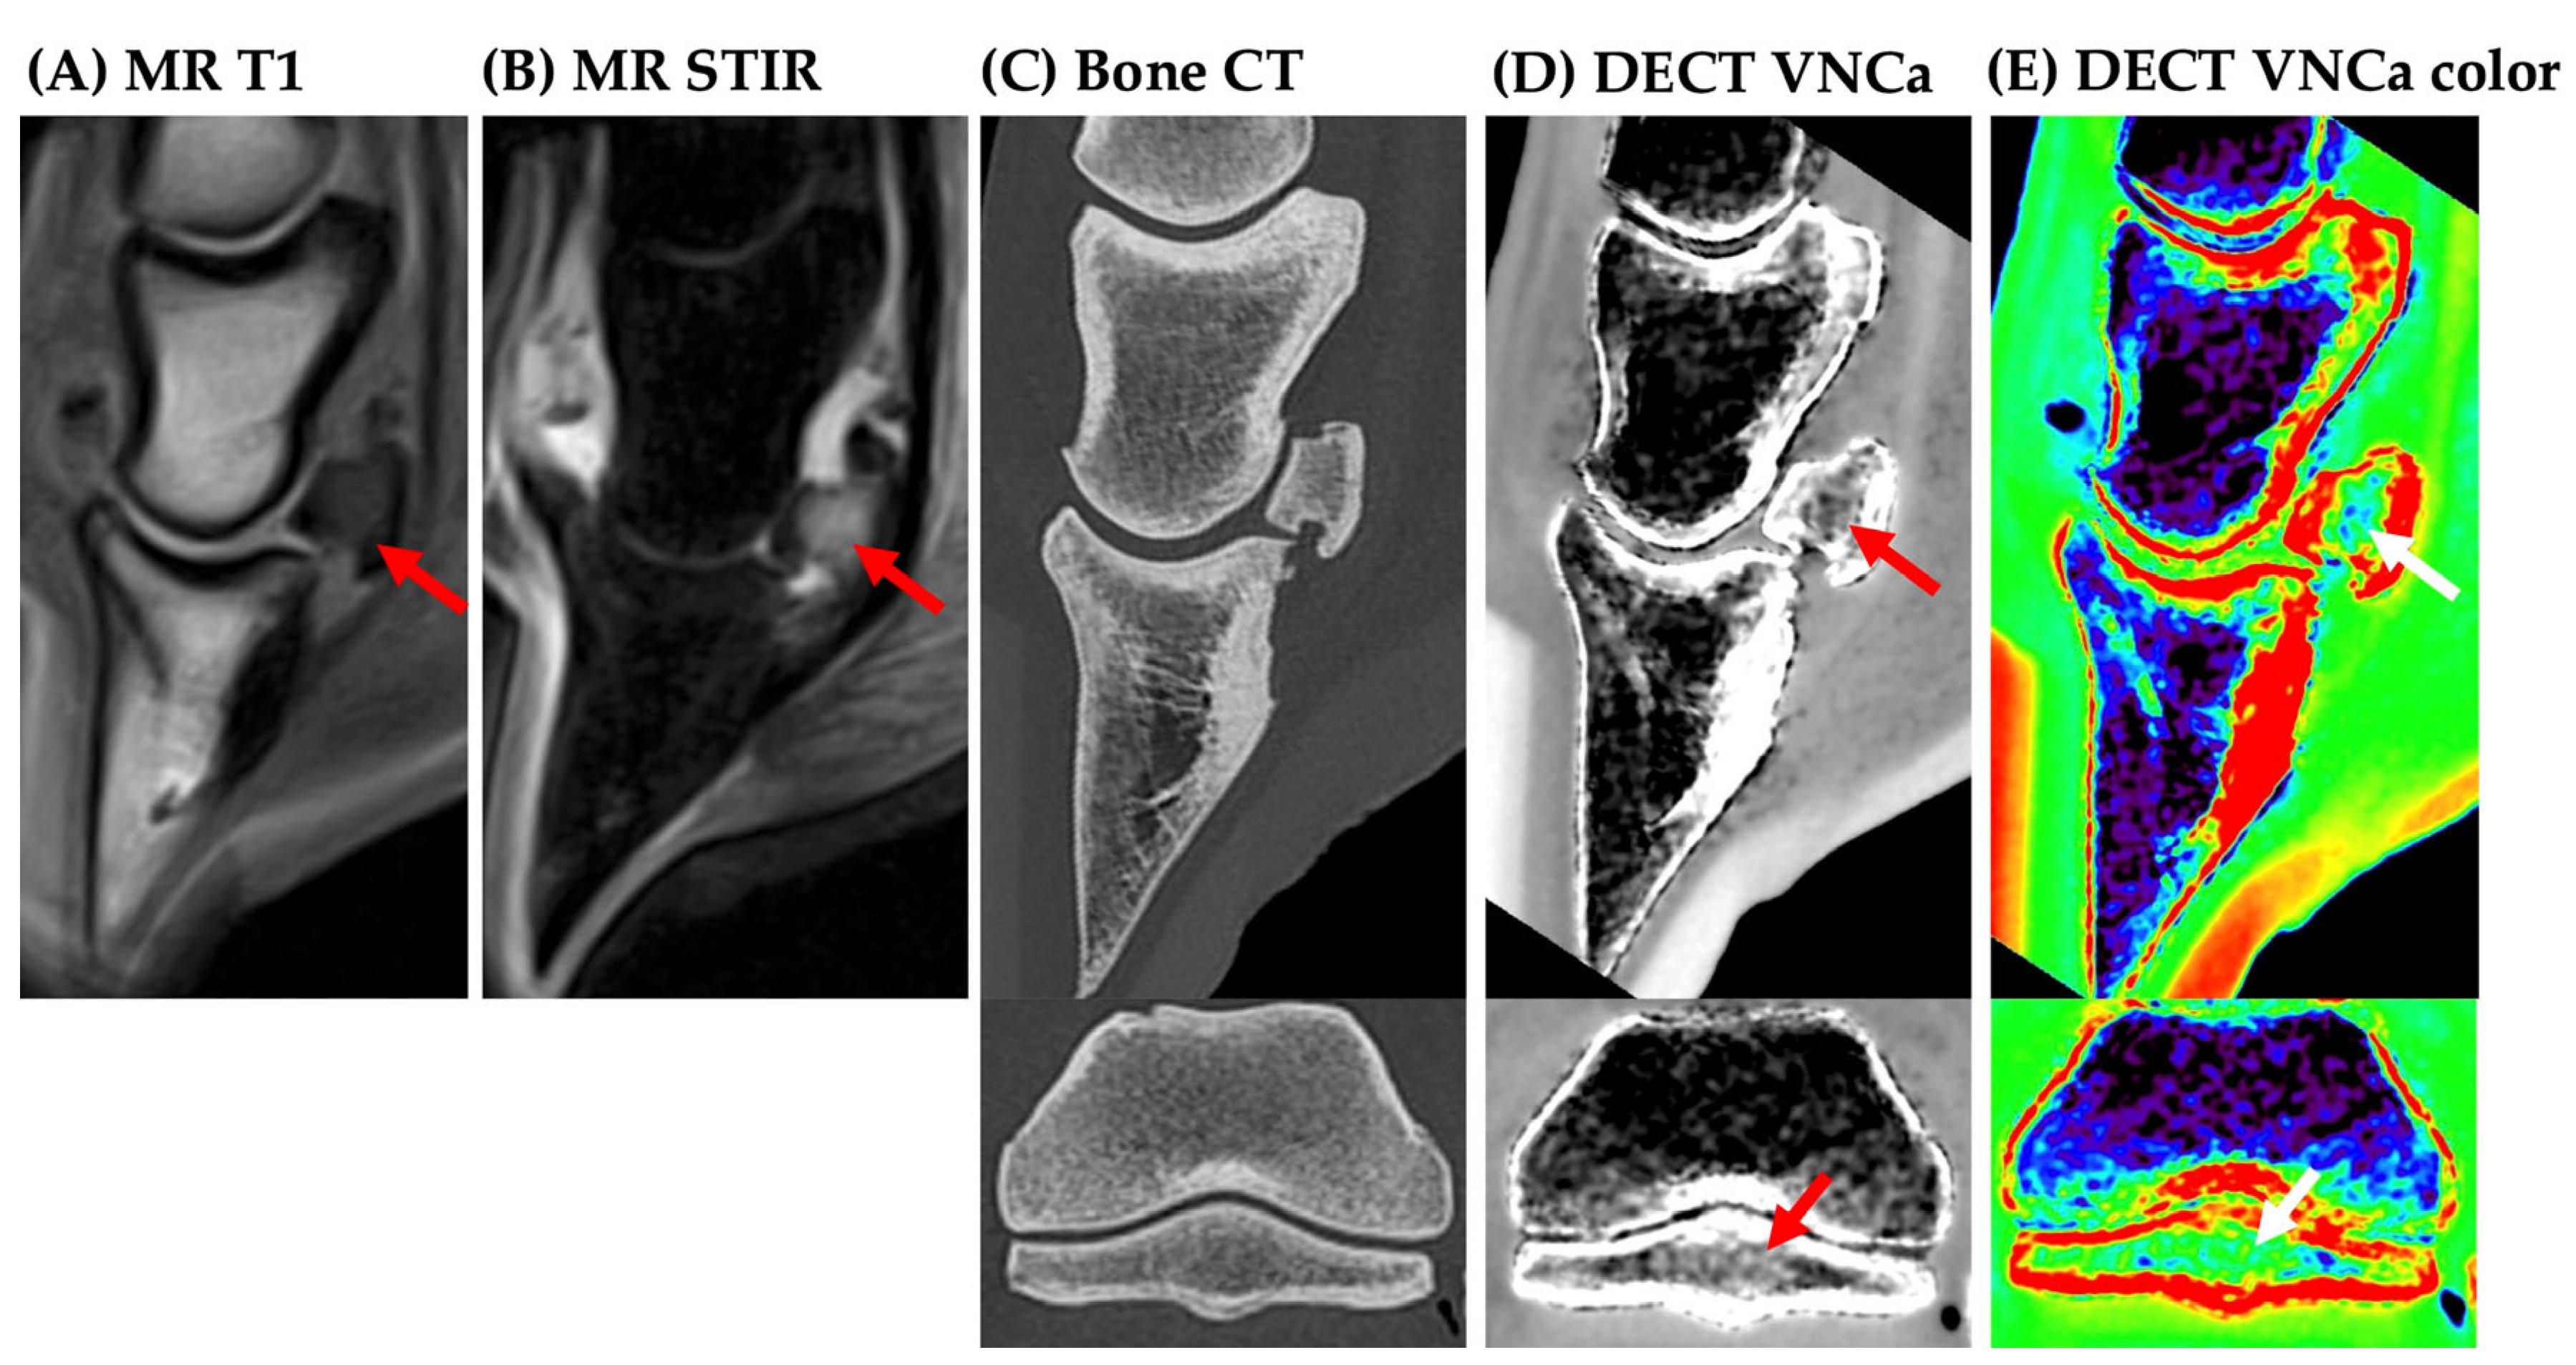

1. Introduction